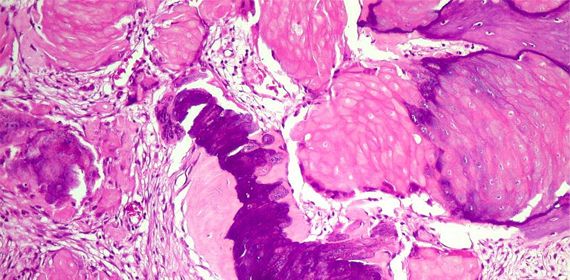

Denso -> tipo de tecido conjuntivo no qual há predominância de fibras colágenas (constituídas de proteína colágeno - apresentam grande resistência à tração e são inelásticas) sobre os outros componentes.

Apresenta menos células, menos flexível e mais resistente. Pode ser subdividido em: Modelado - Regular -> apresenta feixes de colágenos orientados de acordo com uma organização fixa, as fibras orientam-se para oferecer o máximo de resistência as forças que atuam sobre o tecido, sendo encontrado nos tendões e ligamentos cartilaginosos e elásticos;